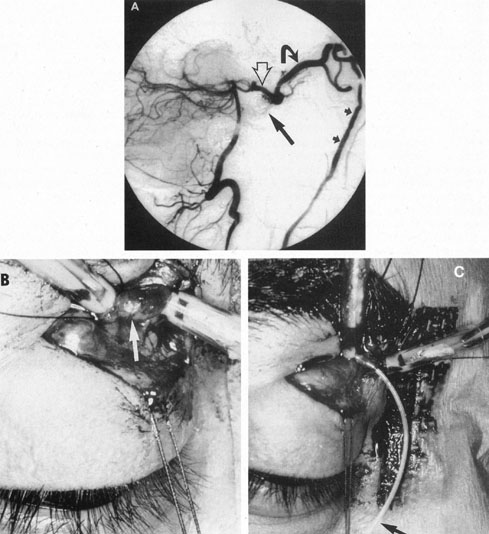

The therapy for AVMs has been reviewed elsewhere.91–93 The preferred treatment remains complete surgical excision of the malformation. However, significant advances in endovascular and radiosurgical techniques have resulted in a marked increase in the use of multimodal, staged approaches to AVM treatment. A variety of intravascular techniques use embolization91 with materials such as particles of polyvinyl alcohol (PVA), platinum coils, and injection of liquid N-butyl-cyanoacrylate (NBCA) adhesive (Fig. 11). Complications of intravascular embolotherapy include vessel perforation by the catheter, migration of embolic materials, and infarction and hemorrhage of normal brain.

Fig. 11. Embolization of middle cerebral vessels that supply occipital lobe arteriovenous malformation (AVM). The patient had a subarachnoid and intraparenchymal hemorrhage that produced a left homonymous field defect. A: Right carotid arteriogram demonstrates contribution via posterior communicating artery to a right occipital lobe AVM. B: Vertebral injection. The arrow points to the enlarged right posterior cerebral artery that is a major feeder of the AVM. C: Right carotid arteriogram during glue embolization procedure. The arrow points to a catheter as it traverses the segment seen in (B). The catheter was advanced via the internal carotid artery but is positioned far posteriorly. D: Upper branches to the AVM now are occluded, with residual low-flow vascularization via the middle cerebral artery. E: Skull film showing radiopaque glue within the AVM and blood vessels previously supplying it. The patient had a persistent visual field defect but greatly reduced headache and no persistence of subjective bruit. (Courtesy of Dr. Joseph Horton.)

Occasionally, transvenous access to the cavernous sinus is thwarted by variations in otherwise normal native anatomy. For example, some compartments of the cavernous sinus involved with the shunt may be completely separated from the inferior petrosal sinus, with exclusive drainage to the superior ophthalmic vein. In such patients, transvenous access can be gained by retrograde catheterization of the superior ophthalmic vein (Fig. 21), either directly128 or by puncture of the facial vein.129 Events may conspire at times to preclude ipsilateral transarterial therapy and thereby necessitate transvenous placement of GDC coils in the cavernous sinus while simultaneously protecting the parent carotid vessel by non-detachable balloon reconstructive technique.130 Use of a coronary stent across the fistulous segment of a direct CCF and subsequent introduction of GDC coils into the sinus via the interstices of the stent has been reported when the anatomy precluded detachable balloon placement.131 When the venous drainage from the cavernous sinus is directed exclusively to the veins of the temporal lobes or to the basal vein of Rosenthal, surgical exposure of the cavernous sinus and intraoperative venous packing with coils may be necessary.